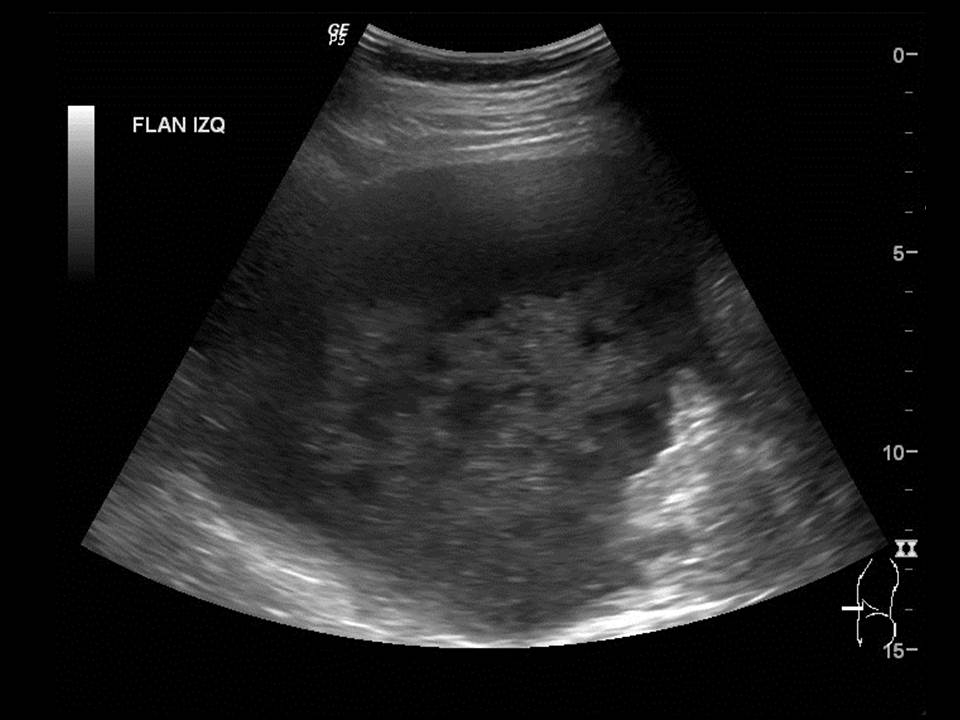

Cuadro clínico de 1 mes de evolución caracterizado por distensión abdominal e hiporexia.

Mujer de 57 años.